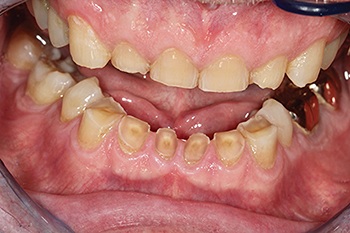

Severe tooth wear, a collapsing bite, and a patient whose livelihood depended on his voice; this was the challenge presented to Dr. C. Terrence Shaw. Referred by a friend while on tour, professional singer John McDermott sent Shaw iPhone photos and radiographs for review. Instead of a lengthy, invasive plan involving orthodontics and multiple crowns, Shaw proposed a minimally invasive, additive solution using direct composite.

At presentation, the patient showed significant wear on the anterior teeth, with the lower incisors nearly absent from view and occlusion severely flattened (Fig. 1). The maxillary bicuspids sat buccal to their lower counterparts. The patient reported no pain, and radiographs showed no active pathology.

Fig. 1: Pre-op wear

Conventional treatment plans had leaned toward orthodontics, multiple crowns, and possible elective root canals, requiring significant time and expense. However, as a professional singer, McDermott declined orthodontic treatment because he didn’t believe he could perform with wires running around his mouth. Shaw instead offered an alternative: rebuild the dentition chairside using direct composite, focusing on restoring form, function, and aesthetics while preserving as much natural structure as possible.